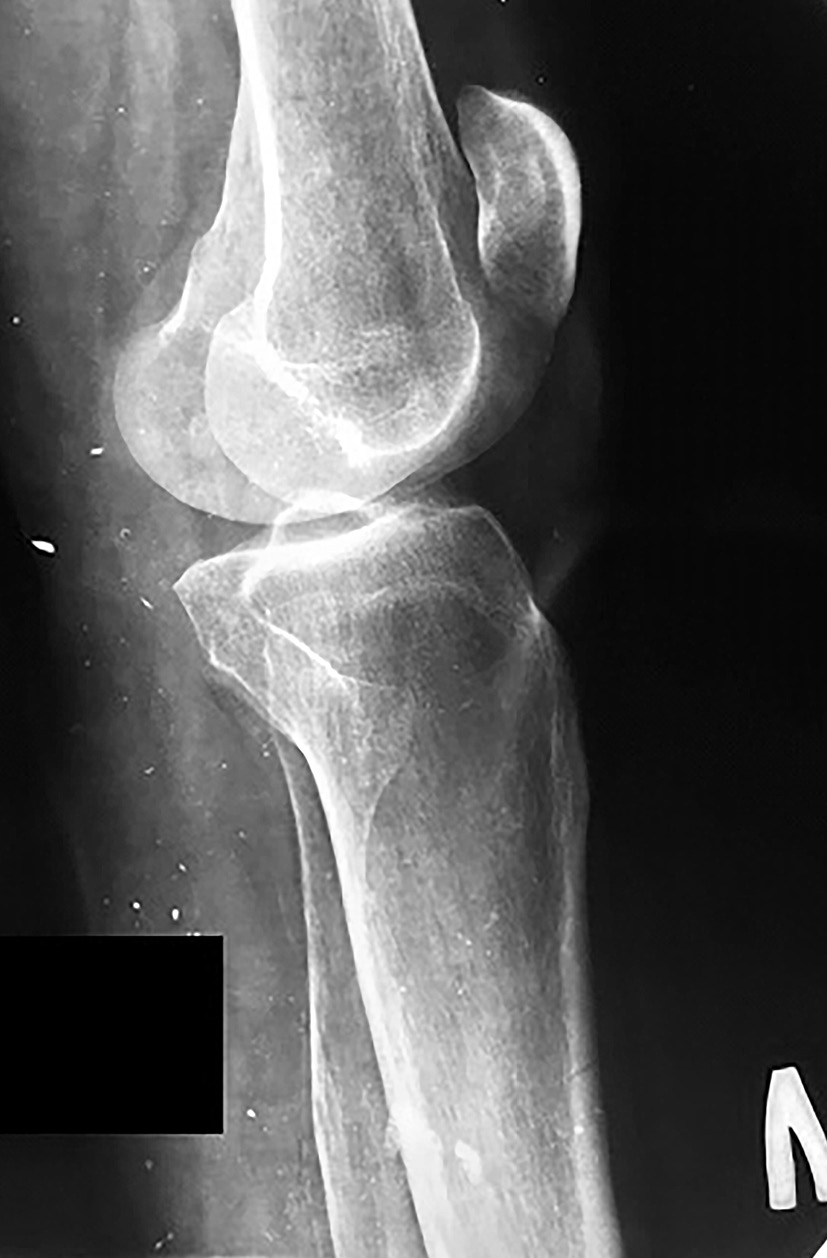

В 1996 г. в остеоартропатический процесс был вовлечен локтевой сустав слева (рис. 1).

Рис. 1. Рентгенограммы левого коленного сустава, 1996 г.

С 2009 г. на рентгенограмме коленных суставов отмечался остеопороз, параоссальные обызвествления, справа – деформация суставных поверхностей, расплющивание мыщелков большеберцовой кости с выраженной перестройкой костной структуры, асимметрия формы и размеров коленных суставов (правосторонний артрозоартрит с грубой деформацией суставных поверхностей, диабетическая артропатия) (рис. 2).

Рис. 2. Рентгенограмма левого коленного сустава, выполненная в боковой проекции, 2009 г.